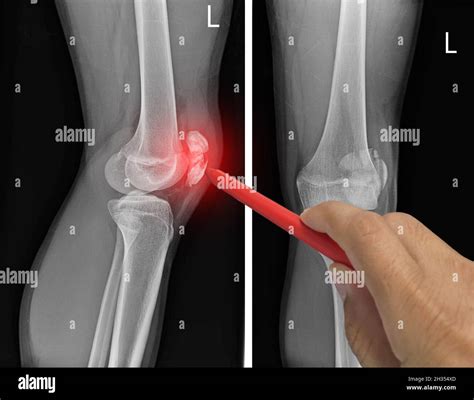

While only an X-ray or MRI can definitively diagnose a fracture, certain clinical signs are strongly associated with broken bones in the knee area. If you notice a combination of these, seek medical attention immediately.

• Deformity: In more severe cases, you may notice that the knee joint appears crooked or the patella is misaligned.

When you arrive at the clinic or hospital, the medical team will likely perform a physical examination followed by diagnostic imaging. An X-ray is the gold standard for identifying fractures, but a CT scan may be required to assess the extent of the damage if the fracture extends into the joint space. Once the extent of the fractured knee symptoms is mapped, the doctor will determine whether non-surgical intervention—such as casting and bracing—or surgical fixation is required.